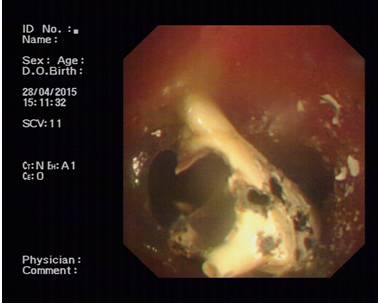

起初,因为没有什么感觉,胡某并不在意。3天后,胡某出现咳嗽气急症状,来到市内一家医院就诊。该院消化化、五官科医生经对他进行胃镜、喉镜检查后,却均未发现异常。由于咳嗽症状加剧呼吸越来越局促,4月27日,胡某经人介绍来到我院呼吸科就诊。经行纤维支气管镜检查后发现,胡某的气管壁黏膜上竟刺嵌着一枚长4.7厘米的巨大异物,经仔细观察,原来是一只蟹脚,于是当即将患者安排住院。患者入院后,该科在学科带头人、副院长俞万钧博士带领下,经过缜密全面的术前检查和评估后,决定用硬镜(硬质支气管镜)联合软镜(纤维支气管镜),对胡某实施钬激光粉碎异物术,以确保在异物清除过程中气管和声带等重要器官不被损伤。术中,负责手术的俞万钧博士小心翼翼地经支气管软镜将钬激光纤维导管插入,然后对准异物进行汽化消融,一点一点把打碎的蟹壳从患者的气管深处取出。由于手术没有一点损伤气管黏膜和出血,术后第2天,患者康复出院。

据俞万钧副院长介绍,钬激光是利用稀有元素钬而产生的脉冲式近红外线激光,波长为2140nm,恰位于水的吸收范围。它通过一种“钻孔效应”能汽化含水的异物如:动物贝壳、骨骼等,导致其表面和内部含有的水分在瞬间高度汽化膨胀,造成无数连续的微小爆破,并且这些微爆破又产生二次冲击波,于是异物如同豆腐碴般在双重微爆下由表及里层层崩解。据悉,联合使用硬质支气管镜和软质纤维支气管镜,采用钬激光取气管内异物在宁波尚属首创。(呼吸科 马坚)

图片2 蟹脚气化